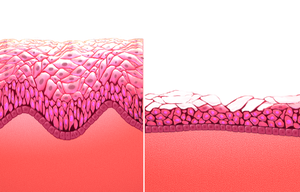

وقد تسبب مستويات الإستروجين المتناقصة، بعض الأعراض مع اقتراب المرأة من سن اليأس. على سبيل المثال، قد تقاسي العديد من النساء من حالات مفاجئة من الحرارة الشديدة والتعرق، تعرف باسم التوهجات الساخنة والتعرق الليلي. وقد تسبب هذه النوبات الشعور بعدم الراحة أو تؤدي إلى انقطاع النوم. كما قد يؤدي انخفاض الإستروجين أيضًا إلى جفاف وتهيج المهبل.